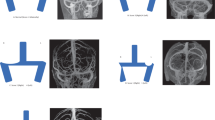

In IVUS (Volcano Corporation, Rancho Cordova, CA, USA) assessment, the luminal lesion border was traced using a slow manual pullback technique at rates of approximately 1.0 mm/s, to calculate the luminal CSA. The reference segments in this study were defined as a segment 5 mm proximal and distal to the stenosis border and were confirmed as healthy segments without stenosis by IVUS. The method for calculating the degree of maximum stenosis of the lesion on IVUS is depicted in Fig. 2.

A diagram presented CVS stenosis induced by arachnoid granulations, accompanied by IVUS images of the resulting stenosis. (A) The diagram desplayed cross-sectional and longitudinal views of CVS stenosis sites caused by arachnoid granulations, along with reference sections from the proximal and distal segments. The blue section represented the CVS, while the black circles in the cross-sections marked the tips of the IVUS transducer. Sections b and d showed the cross-sectional and longitudinal views of the proximal and distal segments, respectively. Section c displayed the cross-sectional and longitudinal views of the stenosis sites caused by arachnoid granulations. Sections a and a1 exhibited significant arachnoid granulations within the CVS, leading to CVS stenosis. (B) IVUS images displayed cross-sectional and longitudinal views of CVS stenosis sites caused by arachnoid granulations. CSA 1 indicated the luminal CSA at the site of the most severe stenosis caused by arachnoid granulation, while CSA2 and CSA3 indicated the luminal CSA at the distal and proximal reference segments, respectively (a’ depicted significant arachnoid granulation within the CVS, resulting in CVS stenosis). The Fig. 2A was generated by Adobe Illustrator CC 2022 (http://www.adobe.com/cn/creativecloud/roc/business.html) .

Three measurements were recorded: the luminal CSA of the site with the most severe stenosis (CSA 1), the luminal CSA of the distal reference segment (CSA 2), and the luminal CSA of proximal reference segment (CSA 3). The formula for the degree of stenosis is (1-[CSA 1/(CSA 2 + CSA 3)/2])100%. The length of CVS stenosis was defined as the distance between the distal and the proximal ends of the stenosis border.